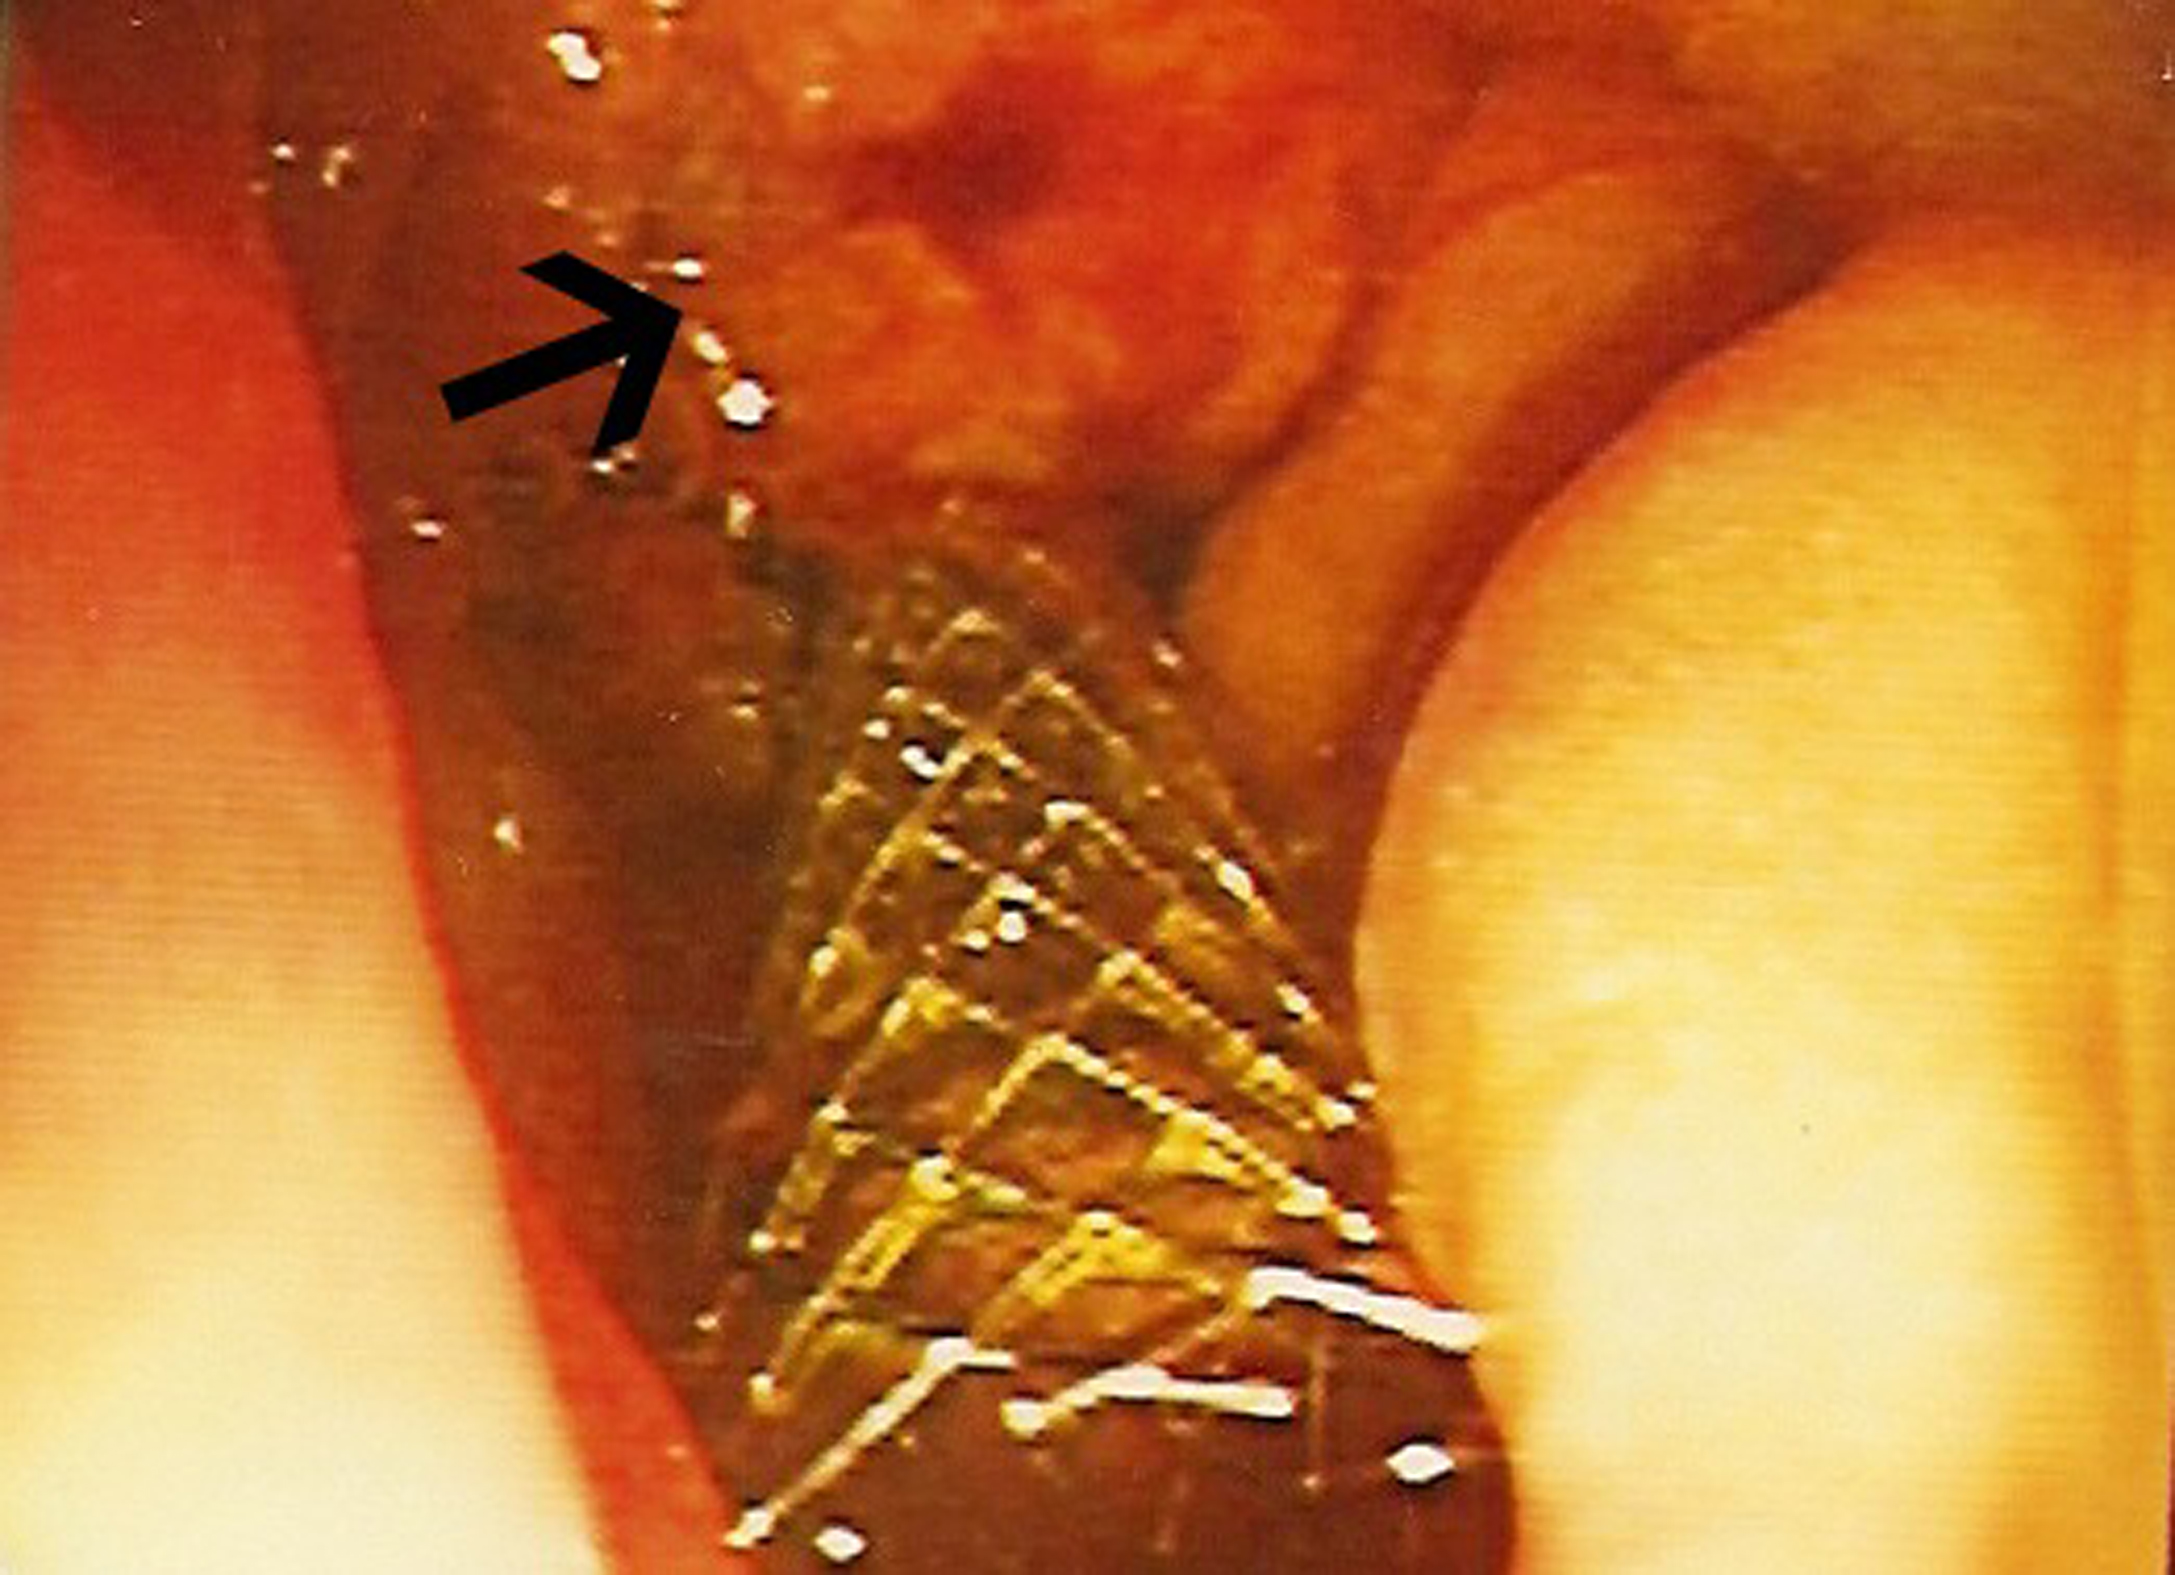

A biliary stent was inserted successfully during the endoscopic retrograde cholangiopancreaticogram (ERCP) (Fig. 2) and satisfactory drainage was achieved. Her liver enzymes and bilirubin improved significantly. A restaging CT showed a 6.0 x 4.5 cm mass involving the uncinate process of the pancreas and second part of the duodenum (Fig. 3, 4). New liver lesions were also seen.

![]() Click for large image | Figure 2. Endoscopic view: black arrow pointing to mass at ampulla of Vater, metallic stent in-situ. |